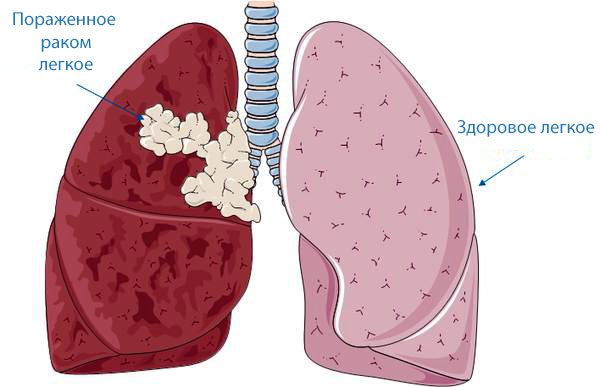

Формирование злокачественного новообразования легких происходит достаточно медленно. Диагностика порою бывает затруднительна, поскольку многие симптомы неспецифичны и принимаются специалистами за проявления иных легочных патологий. Нередко до обращения в специализированную клинику ситуация доходит до крайности – у пациента диагностируют уже рак легких 4 степени, что существенно затрудняет лечение и ухудшает прогноз выживаемости.

Отсутствие явных признаков расстройств деятельности дыхательной системы существенно затрудняет адекватную диагностику рака легких 4 стадии – пациентом слабость и малопродуктивный кашель воспринимаются, как симптомы иных легочных патологий, к примеру, хронического бронхита.

Изменения в органах человека в этом случае практически не обратимы – последняя стадия рака легких для многих больных звучит, как смертельный приговор. Все симптомы рака, присущие именно 4 стадии заболевания, можно подразделить на общие, взаимосвязанные с раковой интоксикацией, и специфические, появившиеся именно из-за метастазирования.

Рак легких 4 стадии имеет и специфические проявления – дыхательные расстройства. На 2-3 этапе формирования патологии они не столь показательны, но к моменту выхода метастазов в иных органы, степень их интенсивности такова, что постановка адекватного диагноза не вызывает у специалистов затруднений.